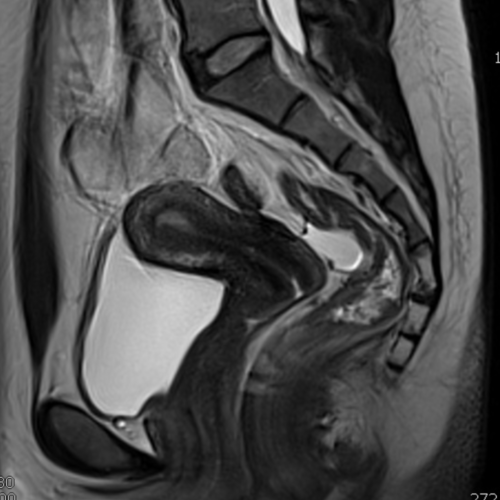

Cet examen est réalisé pour analyser l’utérus, les ovaires, les ligaments uto-sacrés, les veines pelviennes, la vessie, le rectum. Il est réalisé en cas de douleurs pelviennes, dysménorhées, saignements anormaux, métrorragies, ménorragies, dyspareunie, endométriose.

Quels sont les résultats possibles d’une IRM pelvienne ?

Cette examen permets de diagnostiquer:

- l’adénomyose

- l’endométriose

- les ovaires polykystiques (SOPK)

- les tumeurs

- les cancers de l’endomètre, du col de l’utérus, des ovaires

- les kystes ovariens classés selon O RADS

- les varices pelvienne